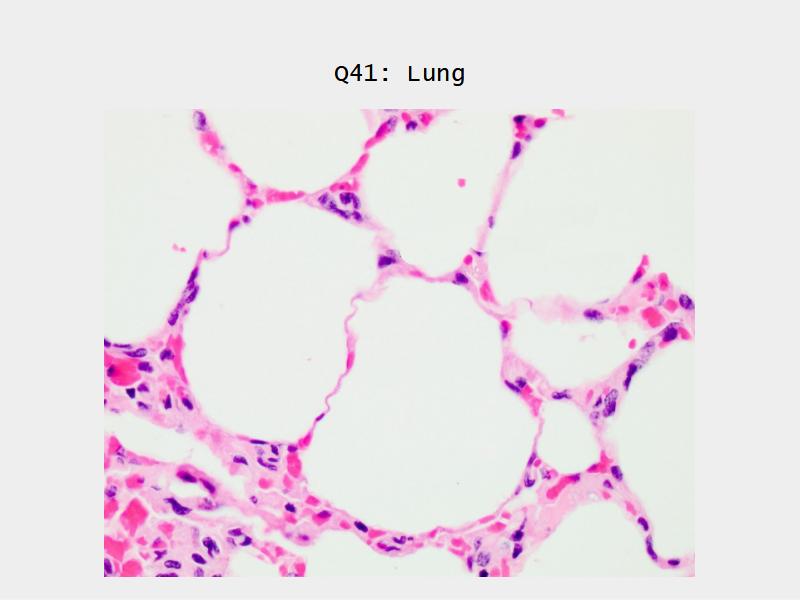

- Slide 72 & 74: Lung

- Alveoli

Lungs